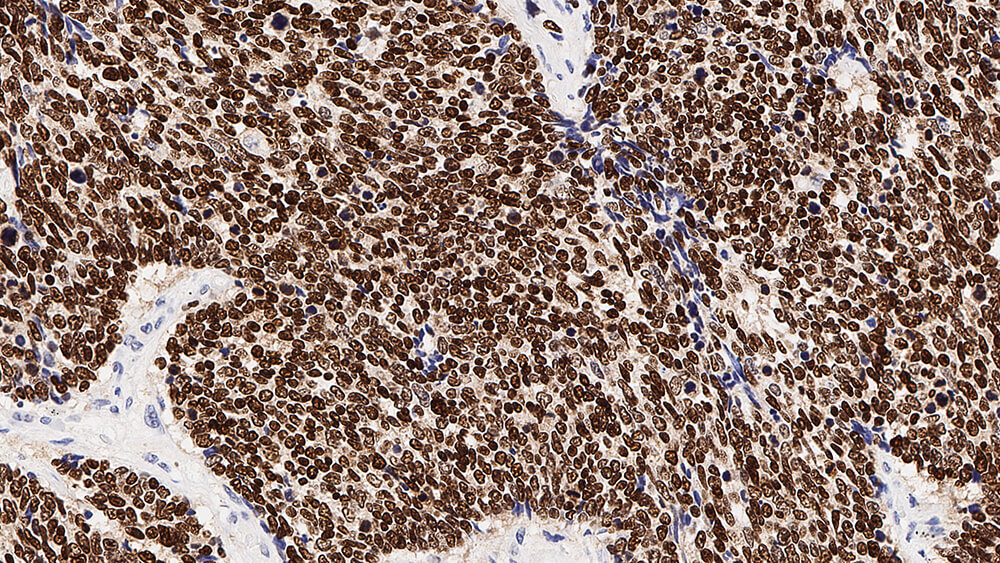

Human thyroid: immunohistochemical staining for Thyroid Transcription Factor-1. Note nuclear staining of thyroid epithelial cells. Thyroid Transcription Factor-1: clone SPT24

Thyroid Transcription Factor-1 (TTF-1) is a member of the homeodomain transcription factor family and plays a role in regulating genes expressed within the thyroid, lung and brain. These include thyroglobulin, thyroid peroxidase, Clara cell secretory protein and surfactant proteins. Human TTF-1 (38 kD) is a single polypeptide of 371 amino acids sharing 98% homology with the equivalent rat and mouse proteins. TTF-1 functions by binding to specific recognition sites in a manner that may be regulated by both the redox and phosphorylation status of the protein. In addition to its role as a tissue-specific transcriptional activator in adult organs, TTF-1 may also function in organogenesis. Gene targeting studies have shown TTF-1 to be essential for the proper development of the thyroid and lungs and abnormal expression may underline a number of congenital abnormalities.